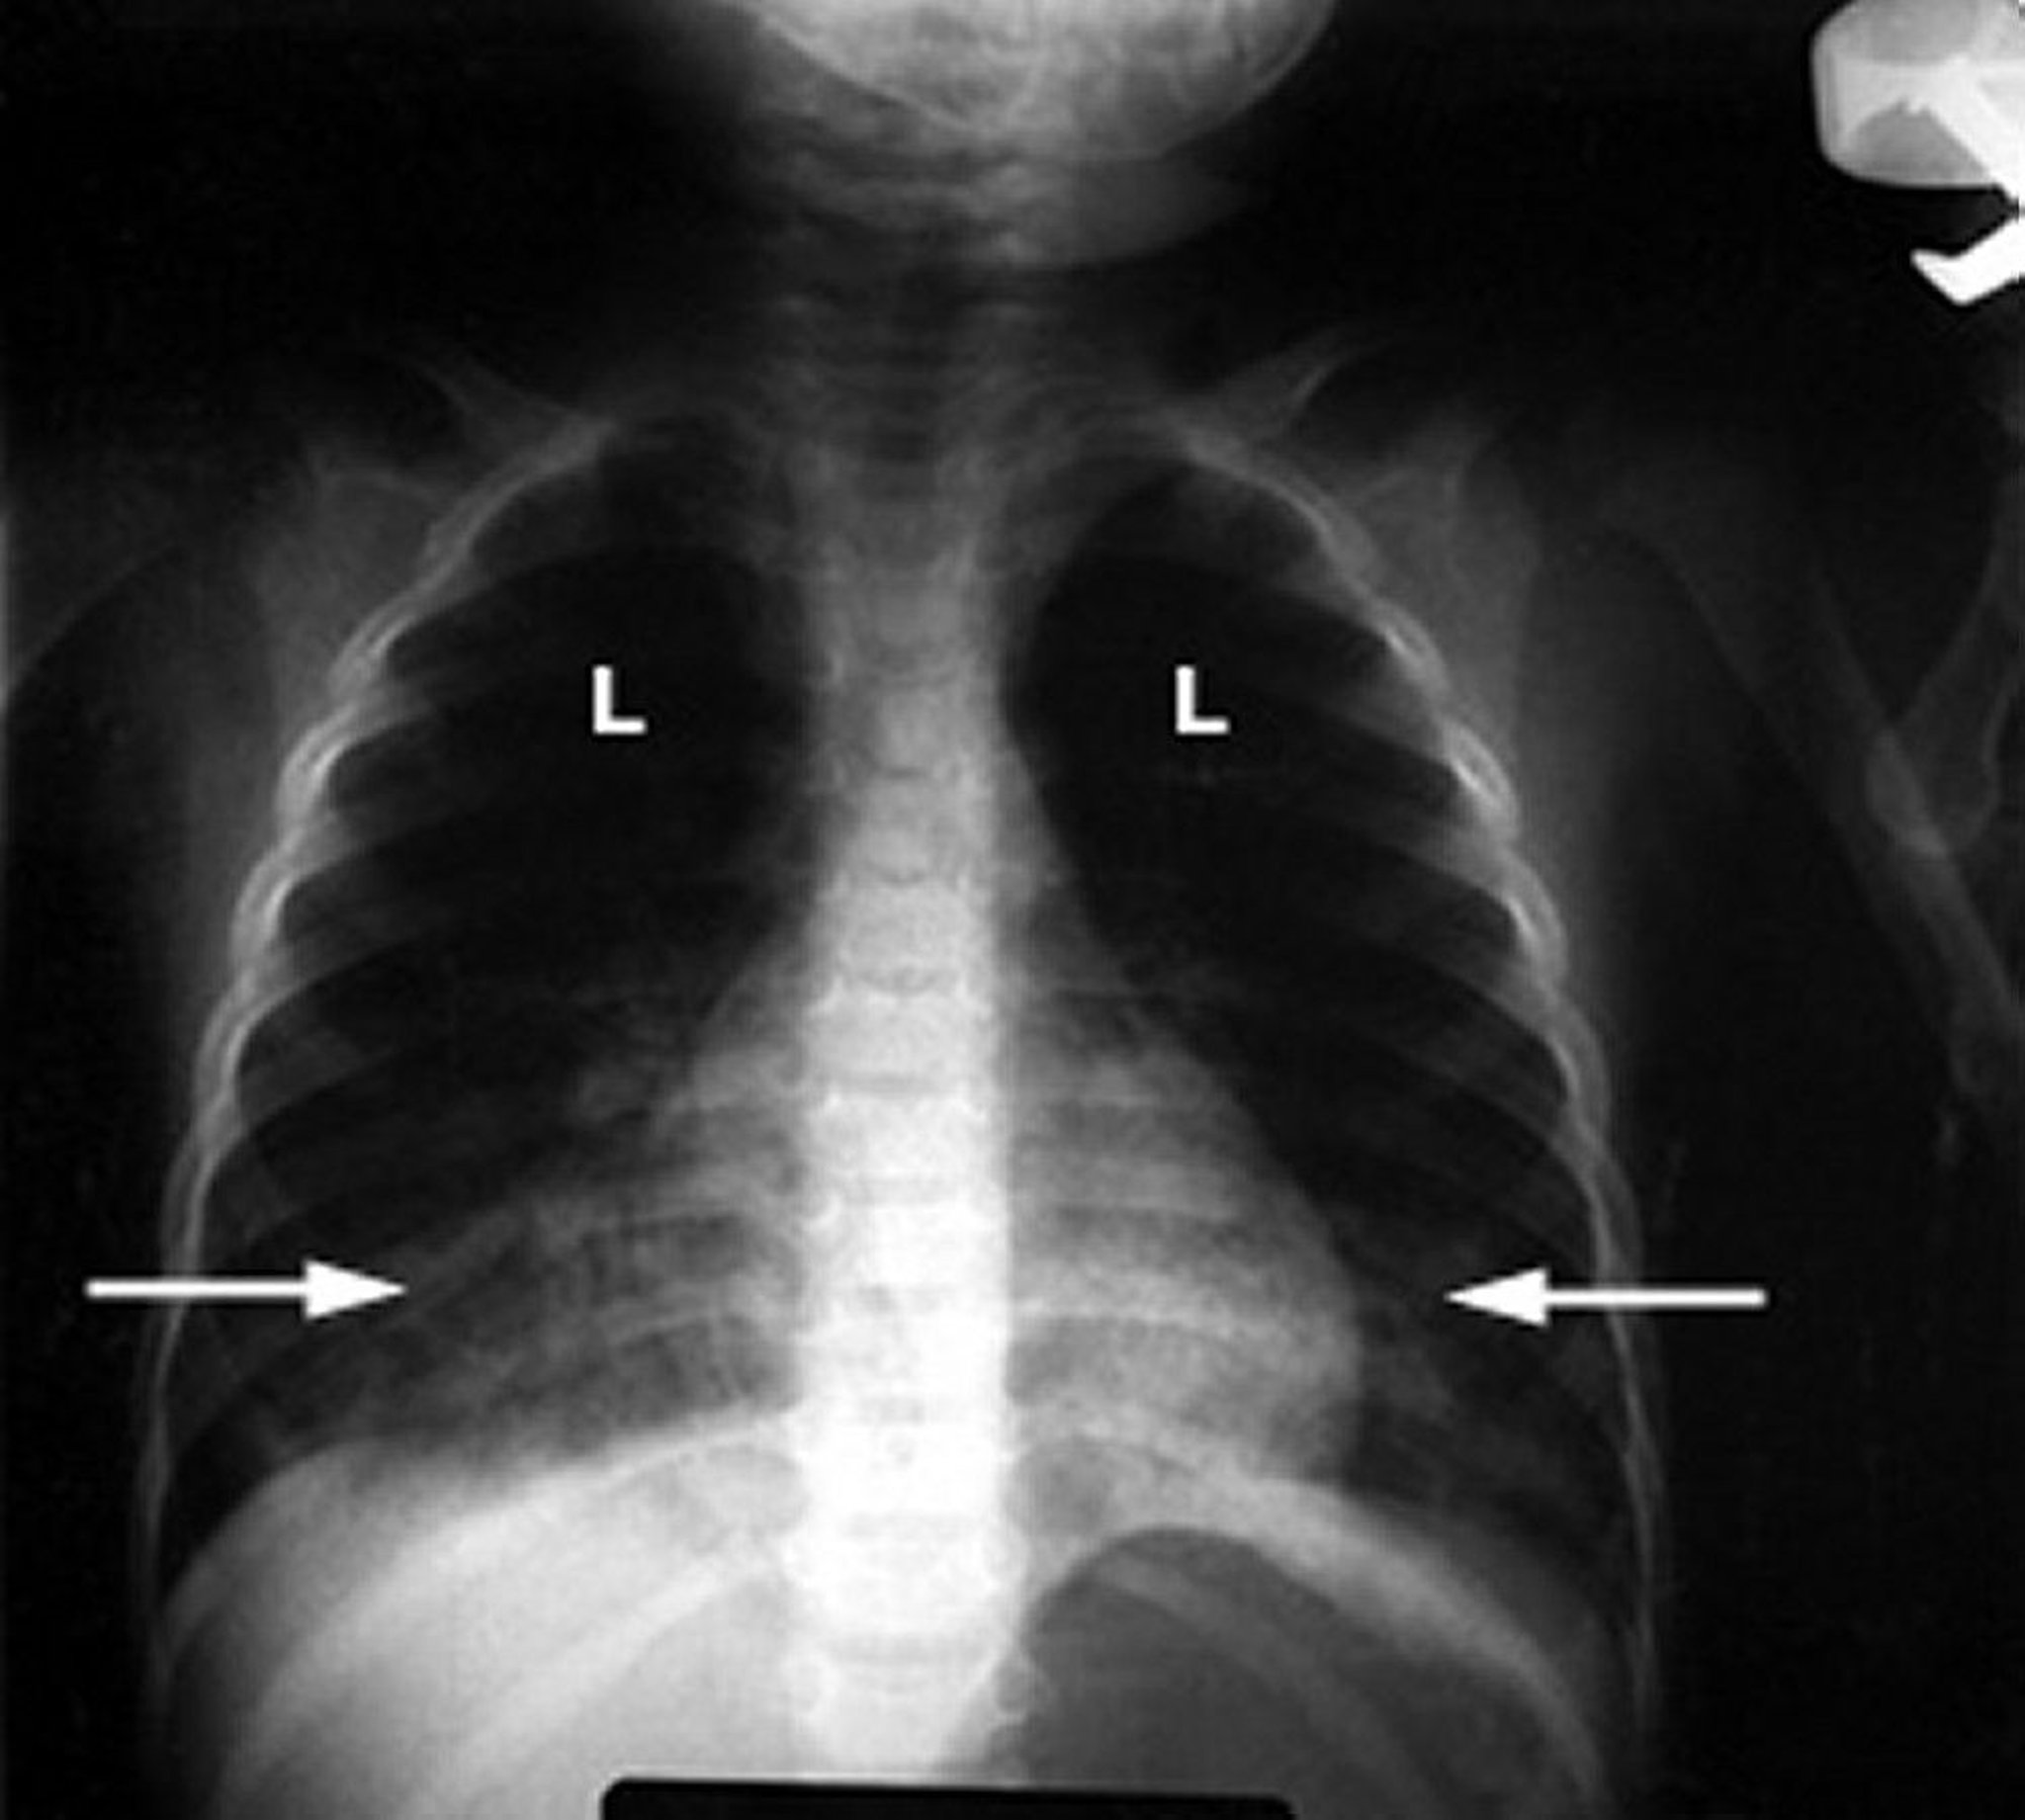

An abnormal chest x-ray in an infant shows white fluffy infiltrates (arrows) in the lungs (L), indicating inflammation. This finding is typical of lung damage due to hydrocarbon poisoning.

Courtesy of G. Schmidt, MD.